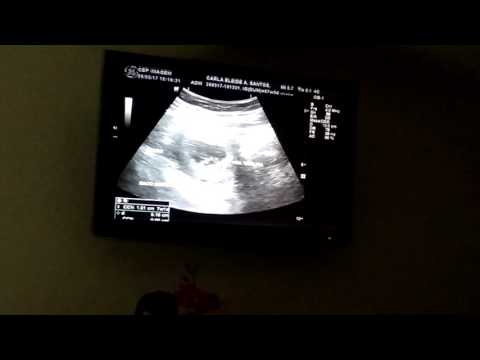

No dia 26/05/17 fomos a clinica de ultrassonografia. Quando entrei na sala do ultra, Serginho entrou comigo. Quando o médico passou a maquininha (não sei o nome, sorry) na minha barriga, tava tudo escuro, aí eu pensei: "ué, cadê o bebê?". Foi quando ele foi regulando o contraste e brilho e foi se formando uma bolinha e ele foi nos explicando que o bebê tava com 1 centímetro e que já era gente, que faltava dois dias pra ele fazer 2 meses (oito semanas). Daí ouvimos o coração de Lorenzo pela primeira vez. Eu não chorei, porque eu imaginei que era uma montagem, eu ainda não acreditava que era verdade, que tinha mais alguém ali na sala, pequeno, se formando, crescendo... Acho que Sérgio teve a mesma impressão. Quando saímos da sala, olhei pra ele e começamos a rir, a gente não tava acreditando porque a gente já tinha passado por muita coisa na outra gestação que não deu certo. Mas graças a Deus, Ele é bondoso e nos deu uma nova oportunidade de termos nosso neném. Foi quando eu entendi que nada é no nosso tempo e tudo é no tempo do Senhor e o tempo Dele é perfeito. Mais que perfeito!

Agora tem um pedacinho do vídeo da ultrassonografia e de quando ouvimos o coração dele pela primeira vez